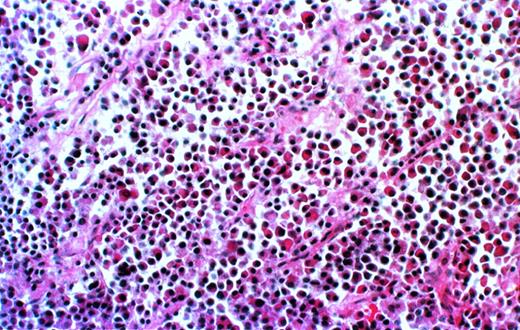

Further analysis is available only for the 8 patients for whom the experiments have been completed. Histological examination of decalcified sections of the human bone showed extensive infiltration of plasma cells (Fig 2). The cells uniformly contained monotypic clg (Fig 3), coexpressed Ig heavy and light chains, and reacted homogeneously and exclusively with the patient’s specific ASO (Fig4), indicating their clonal identity with the original patient’s myeloma cells. In all cases, myeloma plasma cells were found only in the human bone. Neither myeloma cells nor any other human cells were detected in any of the murine organs, bone marrow, or blood, as determined histologically, and by CD38/CD45 and HLA-ABC flow cytometry.

Myeloma cell infiltrate in the human bone of a SCID-hu mouse. Photomicrograph of a 5-μm section of decalcified human bone recovered from SCID-hu mouse (patient no. 4). Hematoxylin and eosin staining, 10× objective.